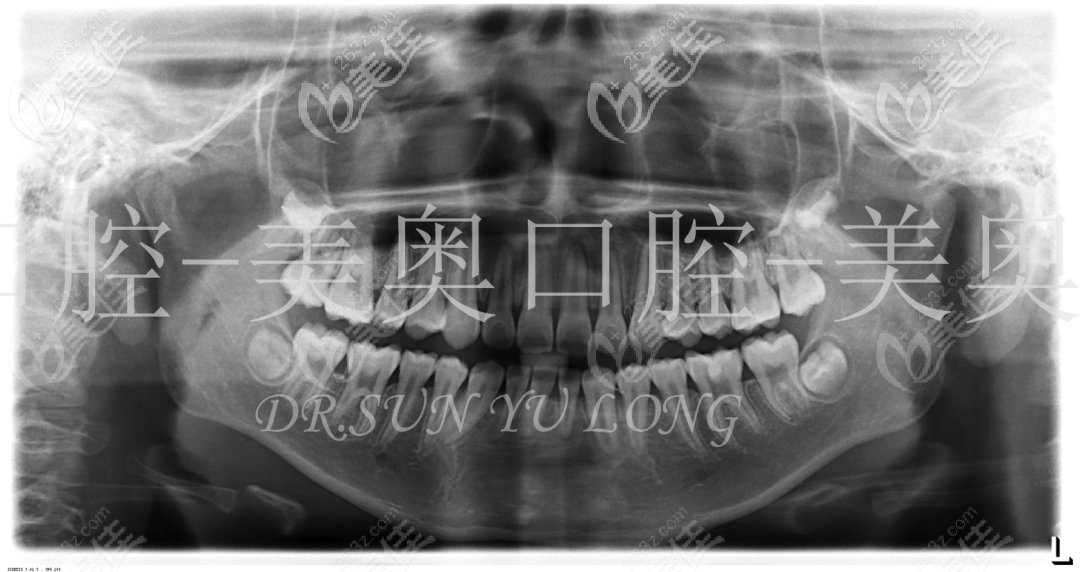

全景片描述:18、28、38、48牙胚存在,41缺失